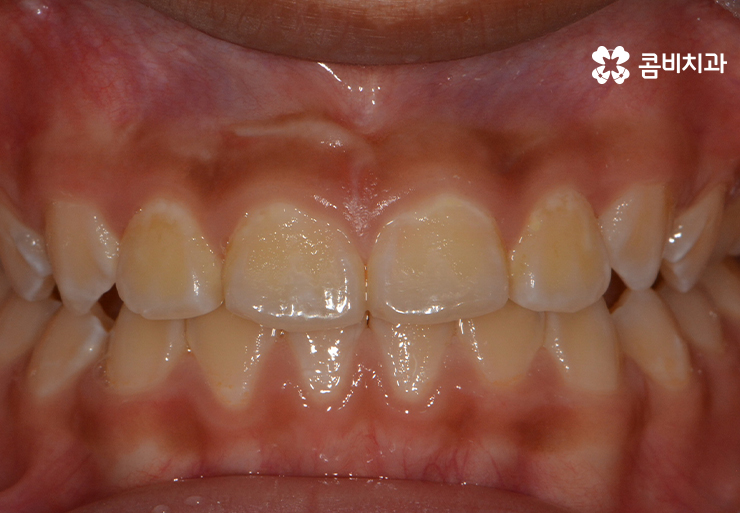

앞니가 반대로 물리고 있던 상황(주걱턱)에서 정상적으로 앞니가 물리게 되었음

(반대교합, 주걱턱 교정치료가 시작된지 1년 후의 모습)

성장기치아교정의 큰 장점 중에 하나라면 성인에 비해서

진료 기간이 단축된다는 점인데 치아의 이동이 빠르고

치주조직이 빠르게 적응을 한다는 점에서도 유리합니다.